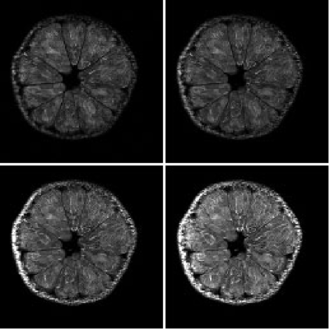

(Insight neuroimaging のご好意により掲載) - ヒトの指先の輪切りの画像

-

爪(青の矢印)がはっきりわかります。結構内部まで入り込んでいるのがわかります。

(産業技術総合研究所 多田充徳博士のご好意により掲載)